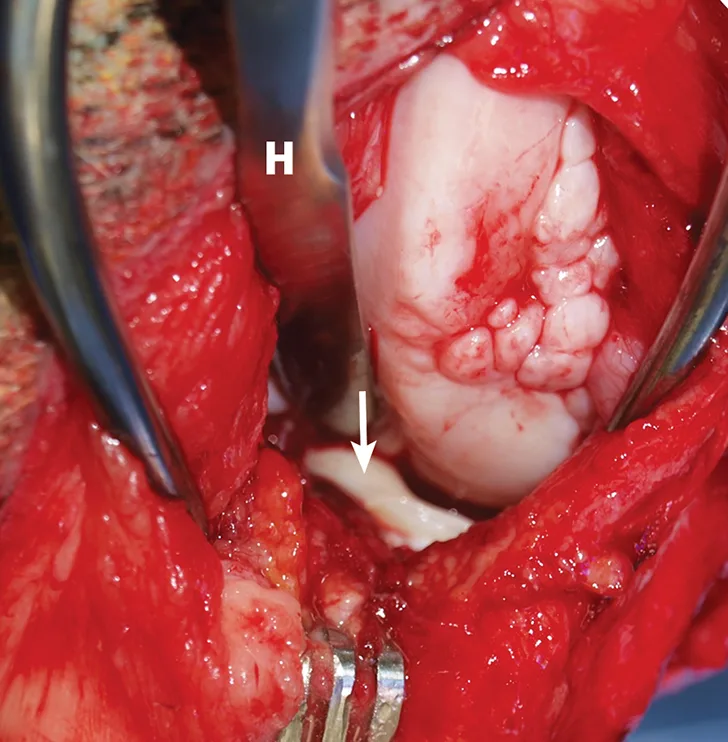

FIGURE 3

Intraoperative image demonstrating identification of medial meniscal tears by craniomedial arthrotomy in the dog in Figure 2. A Hohmann retractor (H) has been placed to allow inspection of the caudal joint space. The caudal pole of the medial meniscus has sustained a bucket handle tear and is flipped cranially (arrow).